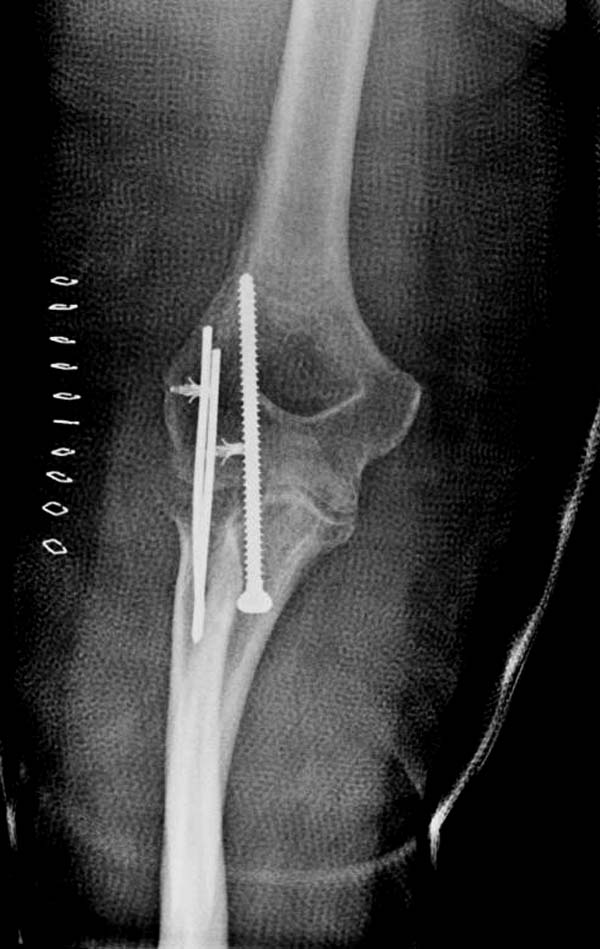

Несмотря на отрицательный отзыв, некоторые нестабильные вывихи лечим

трансартикулярным методом. Тонкие спицы ломаются и имеют риск

внутрисуставной инфекции. Винты 3.5 мм не выдерживают, а более толстые

каннюлированные винты неплохо проявили себя. Неосторожность при

установке приводила к поломке тонких guide wire внутри сустава. Лучшие

кортикальные в 4.5 мм и гипс на три недели. Винт удаляется, затем

разработка сустава.

Снимки: 1-2 вывих, 4-5 вторичное смещение в гипсе, реконструкция

латеральной связки и капсулы 13-14, повторный вывих после реконструкции,

перевод в наш центр; 18-21 временная фиксация, 22-25 трансартикулярная

фиксация и нестабильная головка фиксирована спицами, 29-30 амбулаторно,

Вложение не в текстовом формате было извлечено…

Имя     : 22 Elbow dislocation closed reduction SLU 7.JPG

Тип     : image/jpeg

Размер  : 28223 байтов

Описание: отсутствует

Url     : http://weborto.net:8080/pipermail/ortho/attachments/20131212/4b05a6a3/attachment-0010.jpeg